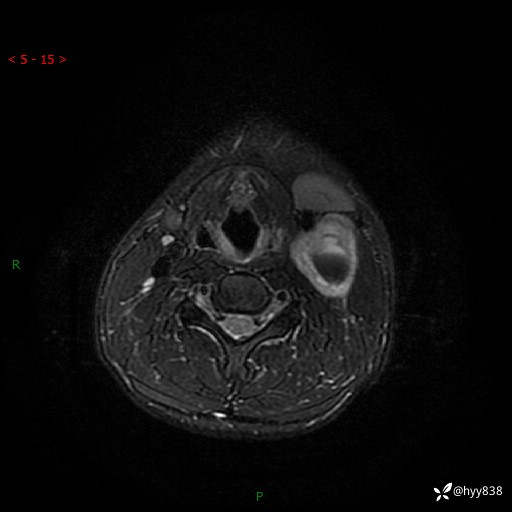

现病史:患者约3年前因感冒发现左侧颈部长一肿物,约半个鸡蛋大小,无明显疼痛及其他不适,一直未行特殊处理。3个月前发现左侧颈部肿物变大,随后至当地市第二人民医院耳鼻喉科行左侧颈部彩超示:左侧颈部囊实混合性包块;喉部MPR示:左侧胸锁乳突肌内前方占位,累及左侧喉旁间隙,建议增强扫描。建议手术治疗。患者考虑。随后至我院肿瘤科就诊,行细胞学穿刺示:考虑血管源性肿瘤可能,建议进一步检查。建议至我院口腔科就诊,行颌面部MRI示:左侧颌下腺后方团状异常信号灶,建议增强。建议手术治疗。为求进一步治疗,门诊以“左侧颈部肿物”收入院。 起病以来,患者神志清、精神良好,饮食睡眠良好,大小便正常,体重未见明显变化。

颈部MRI平扫+增强